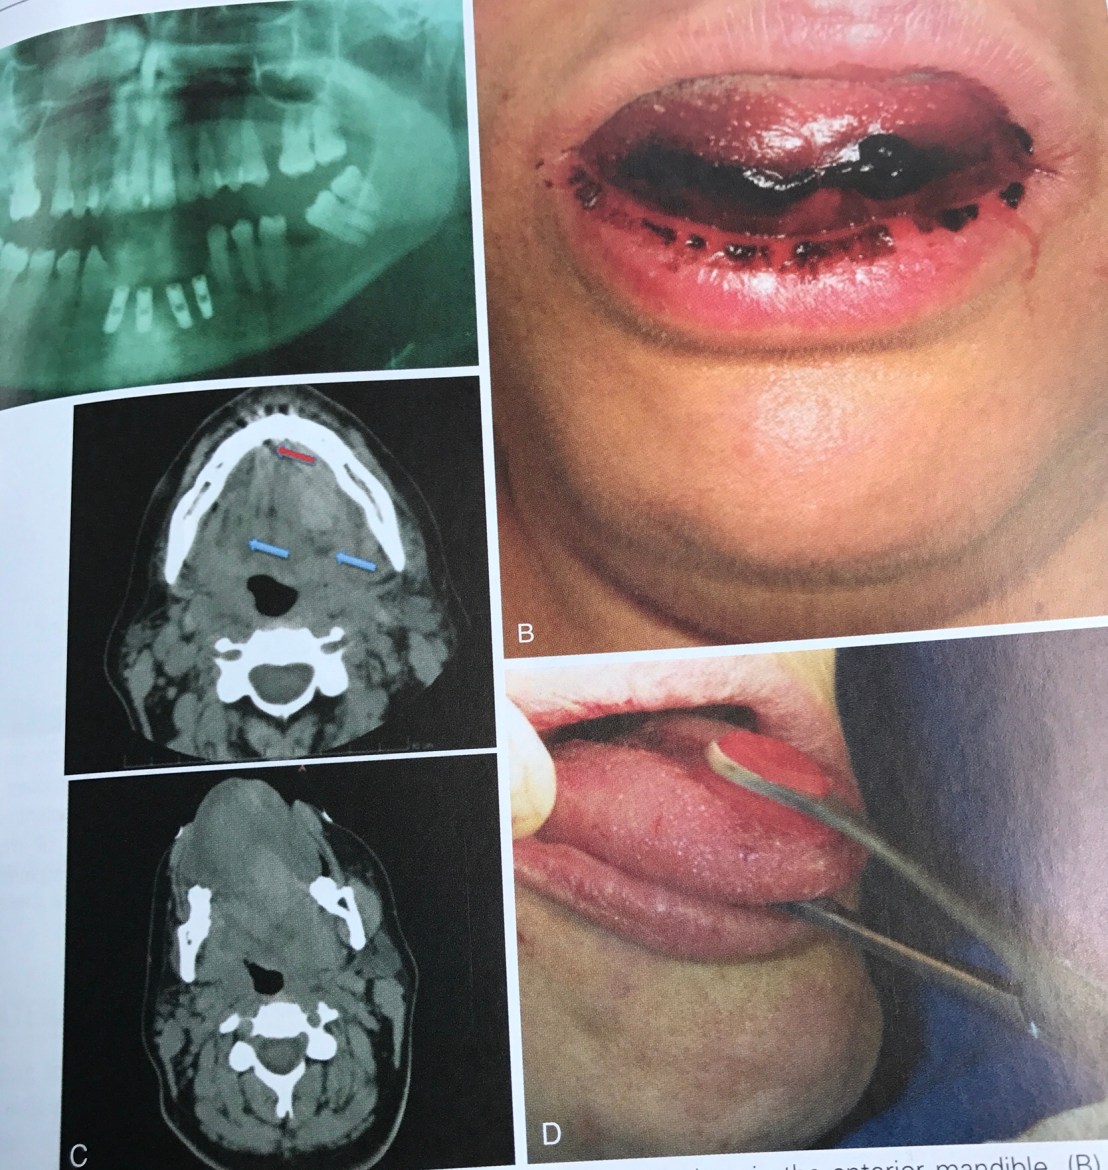

อันนี้ผมเพิ่งเคยเห็น น่ากลัวมาก คือ ฝังไปโดน Sublingual artery ครับ

อันตรายของมันคือ เกิด Sublingual hematoma ไป obstruct Airway

สังเกตฟิลม์ OPG ระดับ Implant อยู่ต่ำกว่า CEJ ของฟันข้างเคียงมาก ปลายของ Implant จึงทะลุ Lingual plate ไปโดน Artery

ในรูป D การใช้ Forceps ดึงลิ้นคนไข้ออกมาเพื่อ stop bleed และเปิด Airway รอทีม EMS มาถึงครับ

รูป Gross แสดง Artery ที่เกี่ยวข้อง และ Film แสดงการ Perforate ชัดเจน

รูป D แสดงการใช้ Bimanual pressure เพื่อหยุด bleed โดยใช้นิ้วชี้กด Gauze ใต้ลิ้นและนิ้วโป้งกดจาก Extra-oral บริเวณใต้คางในทิศดันขี้น